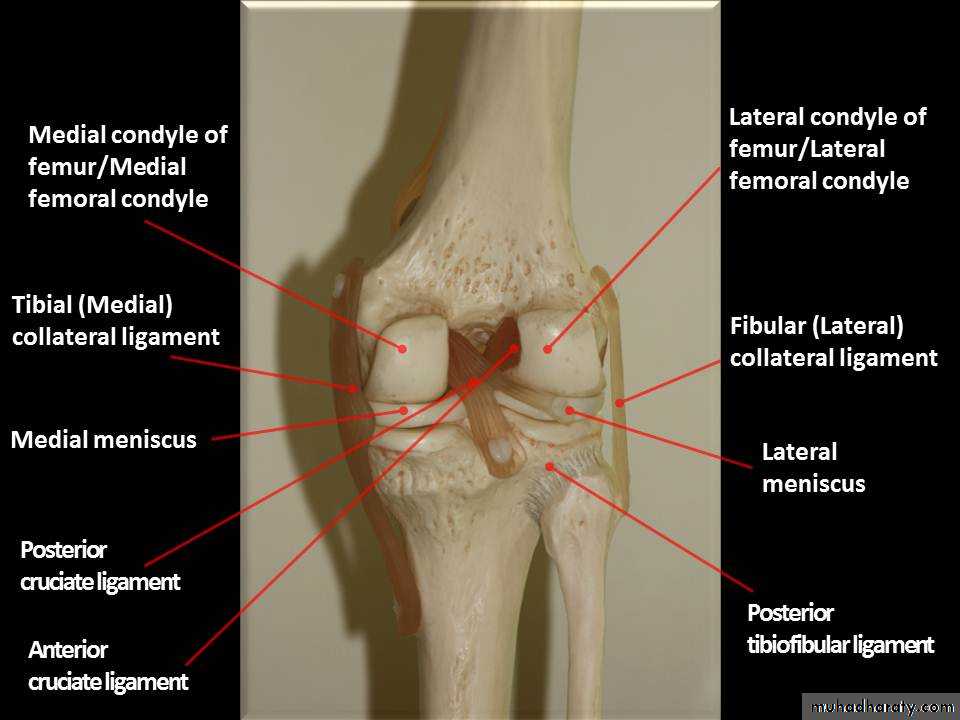

Practical Anatomy of The Lower Limbs for 1st Year Students

Prof.Dr.Abduljabar Alhubaity

Dep.of Anatomy/College of Medicine

University of Mosul